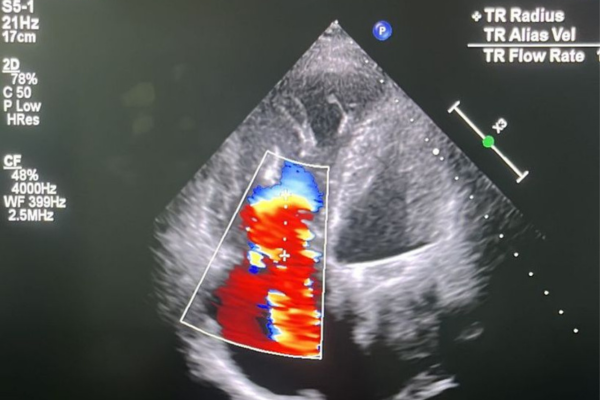

Procedimento relativamente novo tem apresentado bons resultados como a redução da recorrência de internamentos e agora está sendo avaliada a possibilidade de redução de mortalidade dos pacientes.

Recife (PE) – “Já consigo me sentir melhor e menos cansada”, relata a dona de casa Vandilma Queiroz, de 64 anos, quatro dias após ter se tornado a primeira paciente do Hospital das Clínicas da UFPE a realizar o implante de um sistema de válvulas cardíacas, chamado Bicaval Transcateter TricValve. Inédito no SUS em Pernambuco, o procedimento é uma opção de tratamento para a insuficiência tricúspide, caso de Vandilma. A paciente passou pelo procedimento na última sexta-feira (23), na Unidade de Hemodinâmica do HC, hospital que é vinculado à Empresa Brasileira de Serviços Hospitalares (Ebserh).

“Vandilma está reagindo bem. Esse é um procedimento relativamente novo que tem apresentado bons resultados documentados em estudos, como a melhora dos sintomas, a redução da recorrência de internamentos e agora está sendo avaliada a possibilidade de redução de mortalidade dos pacientes”, comenta o cardiologista intervencionista do HC, Edgard Victor Filho, que realizou o procedimento, ao lado de uma equipe composta por profissionais e residentes de Cardiologia, Ecocardiografia e Anestesiologia e equipe de enfermagem.

Esse tipo de insuficiência atinge 1% da população. “A prevalência aumenta com a idade e nos pacientes que apresentam outras doenças valvares como insuficiência mitral ou estenose aórtica. Causando internações repetidas por insuficiência cardíaca”, explica a ecocardiografista do HC Lúcia Salerno, que conseguiu a doação desse sistema de válvulas junto à empresa fabricante.

O procedimento

O sistema implantado em Vandilma Queiroz consiste em duas válvulas autoexpansíveis que são implantadas na veia cava superior e na veia cava inferior. O sistema é indicado para pacientes com insuficiência tricúspide grave, considerados de risco cirúrgico extremo/alto ou não candidatos à cirurgia aberta.  A colocação do dispositivo previne o fluxo regurgitante nas veias cavas, reduzindo a congestão hepática, aumentando o volume sistólico do ventrículo direito para o sistema pulmonar e melhorando o débito cardíaco.

Lúcia Salerno explica que o tratamento da insuficiência tricúspide tem três possibilidades. “A substituição da valva por cirurgia; o reparo da valva por cateterismo com o Triclip; e, nos casos de anatomia desfavorável em pacientes de alto risco, o implante percutâneo da TricValve para diminuir a repercussão da insuficiência tricúspide nos tecidos”, comenta a ecocardiografista.